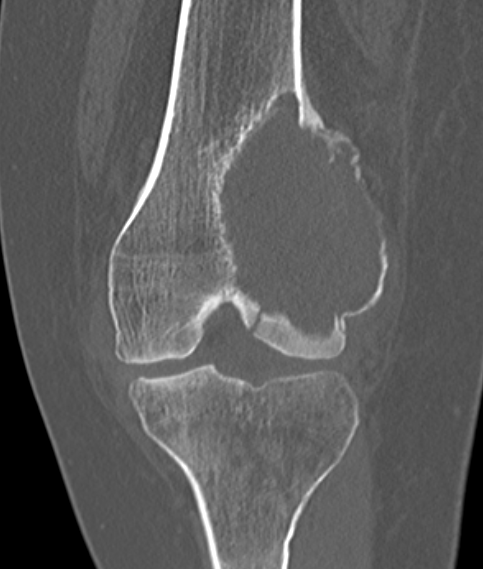

X-ray

Eccentric, sharply demarcated lytic lesion

- no sclerosis around lesion

- narrow zone of transition

- metaphysis, extending into epiphysis

- no mineralization

CT